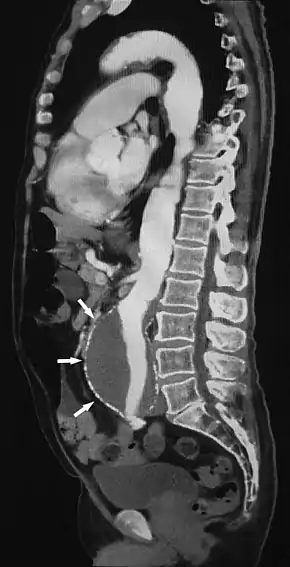

Sagittal thin slice of a computed tomography angiography abdominal aortic aneurysm (AAA) (arrows)

Aorta and great arteries

CTA can be used in the chest and abdomen to identify aneurysms in the aorta or other major blood vessels. These areas of weakened blood vessel walls that bulge out can life-threatening if they rupture. CTA is the test of choice when assessing aneurysm before and after endovascular stenting due to the ability to detect calcium within the wall.[3] Another positive of CTA in abdominal aortic aneurysm assessment is that it allows for better estimation of blood vessel dilation and can better detect blood clots compared to standard angiography.[4]